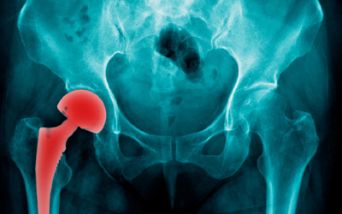

Durante questo periodo della pandemia di Coronavirus molti interventi chirurgici non urgenti, come le protesi d'anca e di ginocchio, sono stati rinviati. In attesa dell’intervento è necessario seguire alcune indicazioni per migliorare lo stato di salute delle articolazioni anche a casa, da soli.

L’Istituto Superiore di Sanità (ISS) consiglia di applicare ghiaccio per limitare il dolore, fare esercizi di stretching a basso impatto per mantenere attivi i muscoli, perdere peso o, comunque, evitare di ingrassare.